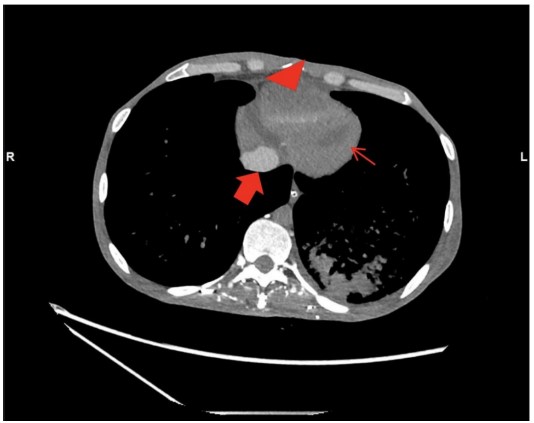

However, the acquisition revealed persistently poor opacification of the pulmonary trunk throughout the imaging interval (Fig. 1). The axial slices demonstrated pathognomonic features of circulatory collapse including dependent layering of contrast within the right ventricle, contrast pooling within inferior vena cava (IVC) and absence of contrast with in the left ventricle and aorta, indicating lack of forward flow (Fig. 2). Due to these highly suspicious findings, the examination was extended to the abdomen, which confirmed pooling of contrast within the hepatic veins (Fig. 3).

The presence of these radiological markers provided definitive evidence that a "silent" cardiac arrest had occurred prior to the contrast injection. Upon recognizing these features, our team immediately transitioned from diagnostic imaging to active resuscitation. Although we achieved the return of spontaneous circulation (ROSC), the patient succumbed to his illness three days later in the intensive care unit.

The hallmark findings in this case were dependent contrast pooling and layering with in the inferior vena cava, hepatic veins, and right heart chambers, accompanied by absent opacification of the pulmonary arteries and left heart. These features reflect a total cessation of effective cardiac output. In the absence of forward flow, the high-density contrast medium (which is heavier than blood) leading to gravitational sedimentation of contrast in the most dependent venous structures. This phenomenon is further characterized by the absence of contrast opacification in the pulmonary arteries and left- sided cardiac structures. The additional observation of contrast stasis in the right heart further underscores the severity of circulatory arrest.